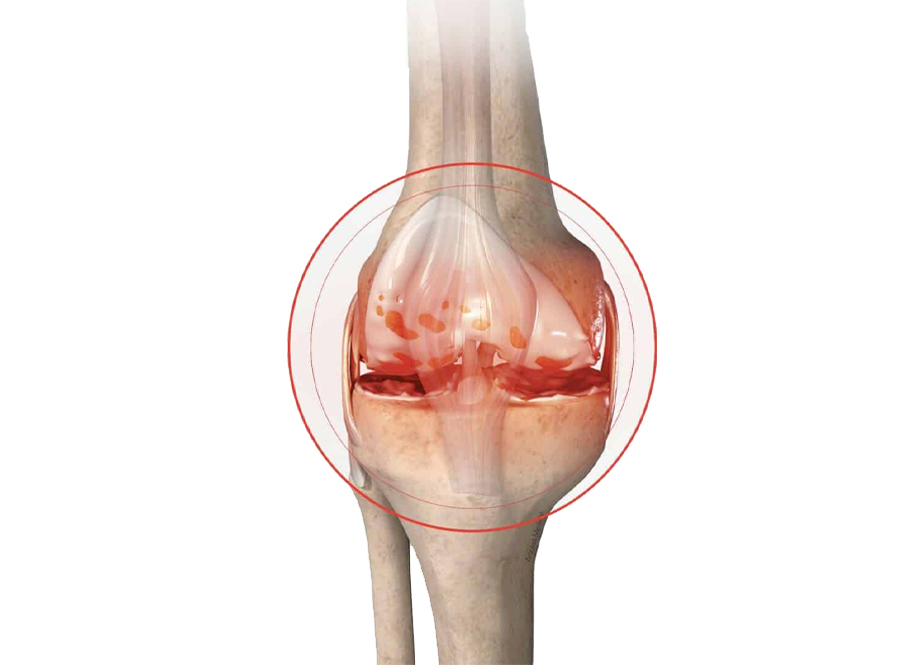

The following are the conditions that can lead to knee replacement failure and may necessitate revision surgery:

After a thorough clinical evaluation, imaging examination, and blood testing, your doctor will determine the reason for implant failure and whether revision surgery is necessary.